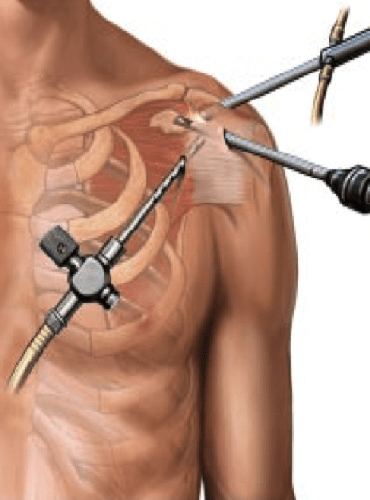

Arthroscopy

Arthroscopy is a surgical procedure orthopaedic surgeons use to visualize, diagnose, and treat problems inside a joint. Joint replacement surgeon in ahmedabad, TKR Doctor in Ahmedabad, Gujarat, Rajasthan.